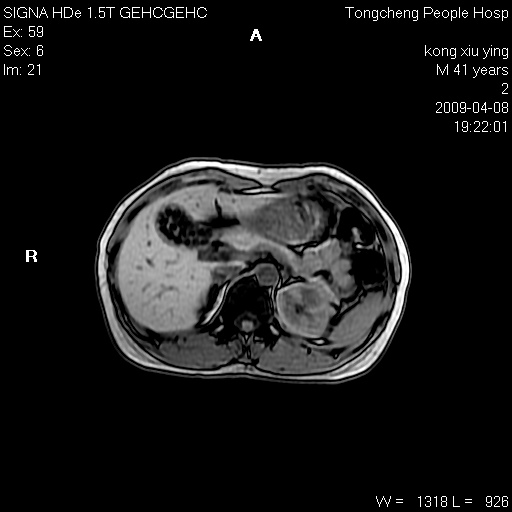

标题: CL1008:【经典】胆囊石榴籽样结石。 [打印本页]

标题: CL1008:【经典】胆囊石榴籽样结石。

女,41岁。健康体检——彩超提示:胆囊显示不清。平素健康,无不适感。

腹部mr扫描及mrcp,图像如下:

胆囊石榴籽样结石。